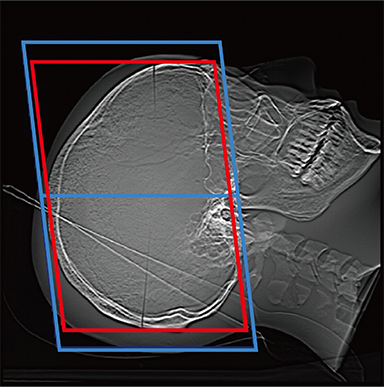

FCT iStream automatically*2 sets the scanning range using the scanogram image by AutoPose function. Since the margins can be set in advance, the range can be customized according to the preference of the facility. iTilt automatically creates and enables observation of tilted images during scanning.

When set to SM Line

Red: automatically set position, Blue: automatically set position + margin setting position